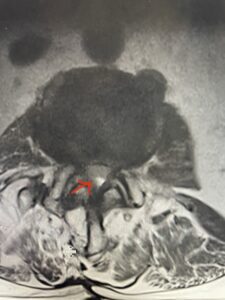

Fig 1b: axial T2-weighted MRI demonstrating severe lumbar stenosis (red arrow)